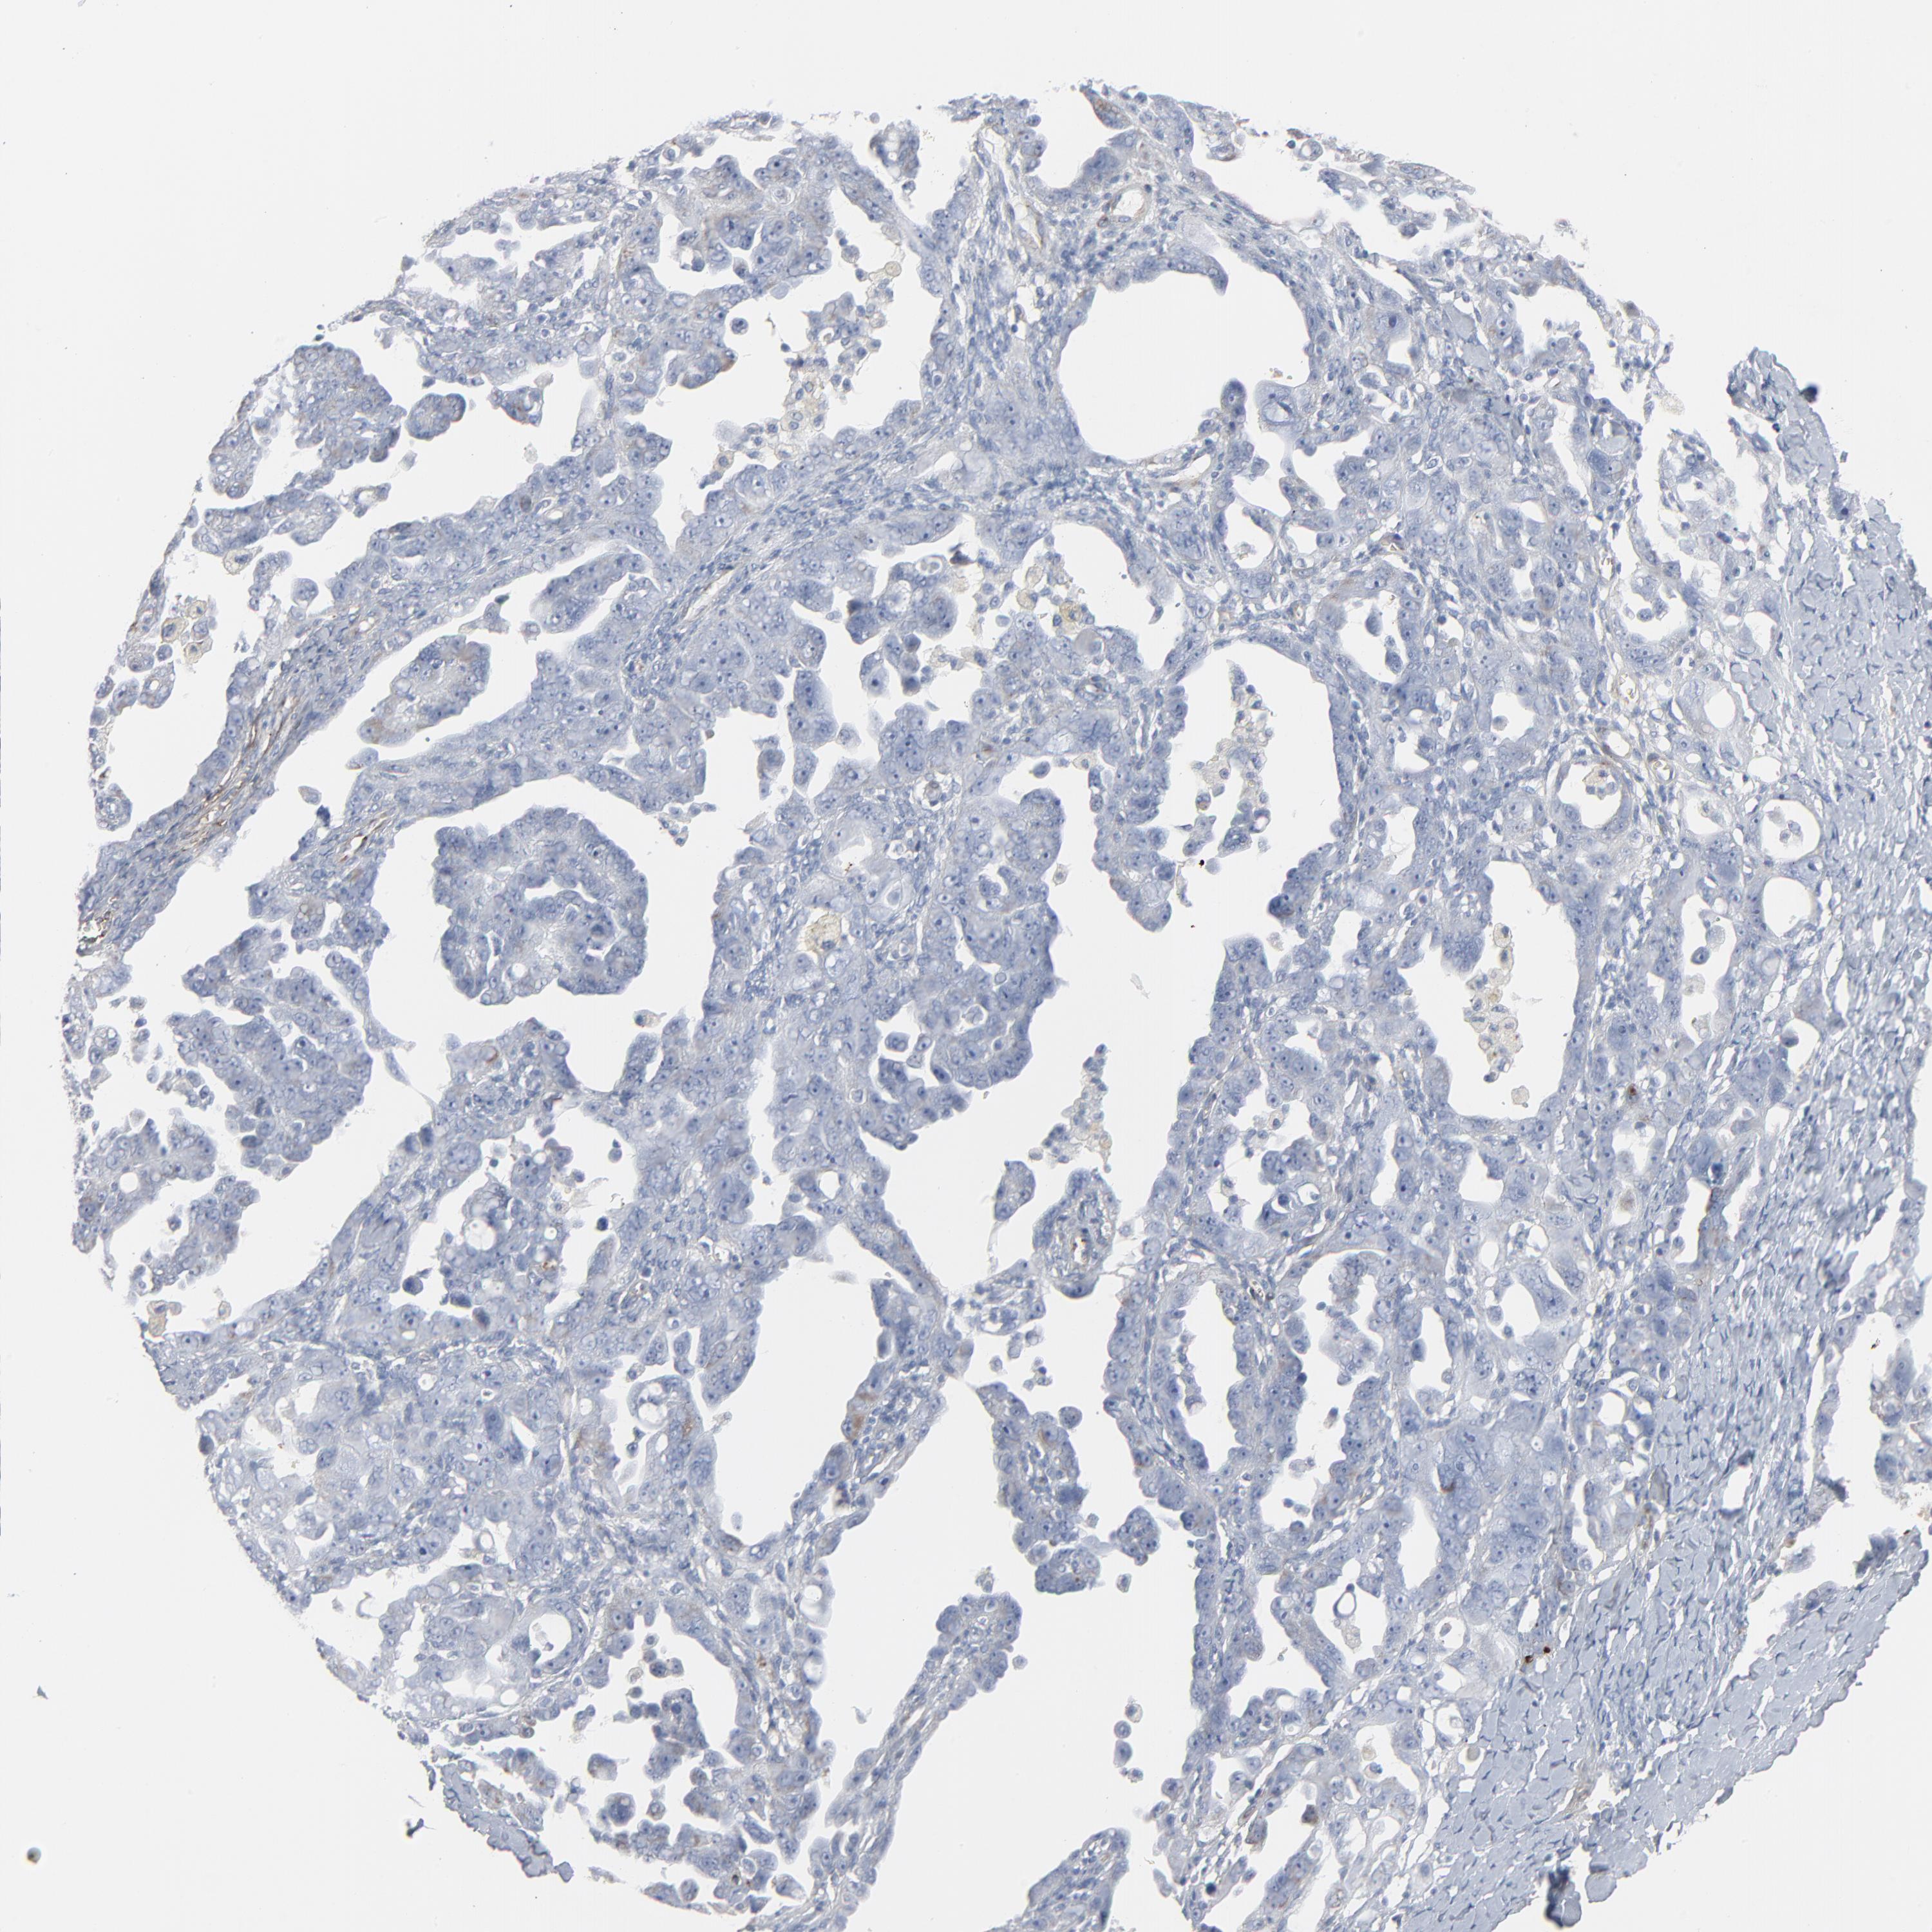

OVARIAN CANCER - Protein expressioni

A mouse-over function shows sample information and annotation data. Click on an image to view it in a full screen mode. Samples can be filtered based on level of antibody staining by selecting one or several of the following categories: high, medium, low and not detected. The assay and annotation is described here.

Note that samples used for immunohistochemistry by the Human Protein Atlas do not correspond to samples in the TCGA dataset.

Antibody stainingi

Antibody staining in the annotated cell types in the current human tissue is reported as not detected, low, medium, or high, based on conventional immunohistochemistry profiling in selected tissues. This score is based on the combination of the staining intensity and fraction of stained cells.

Each image is clickable and will lead to virtual microscopy that enables deeper exploration of all samples and also displays staining intensity scores, fraction scores and subcellular localization as well as patient and tissue information for each sample.

Antibody HPA003157

Antibody CAB003678

Carcinoma, endometroid

Cystadenocarcinoma, serous, NOS

Cystadenocarcinoma, mucinous, NOS